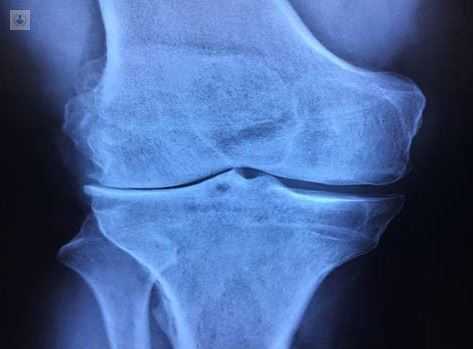

¿Qué es la artrosis de rodilla?

Se estima que la artrosis de rodilla afecta al 30-35% de los mayores de 65 años, estableciendo un pico de prevalencia en el intervalo de edad entre los 70 y 79 años.

En este grupo de pacientes la incapacidad funcional y el dolor, principales síntomas de la artrosis de rodilla, suelen causar una sustancial pérdida de autonomía y calidad de vida. Es por ello que se convierte en un gran problema de salud pública, dado el envejecimiento progresivo de la población, y la cada vez mayor prevalencia de la artrosis.